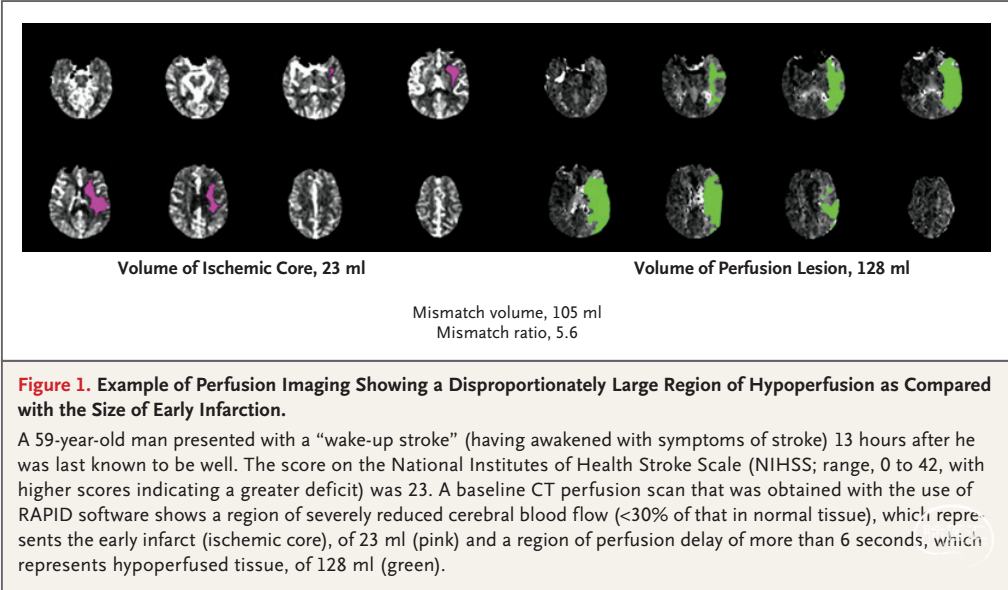

DEFUSE 3(eligibility)

•卒中前mRS<2

•ICA或MCA近端闭塞所致卒中

•年龄:18-90

•NIHSS≥6

•股动脉穿刺能在发病6-16小时内实施

•影像检查存在梗死-灌注不匹配

核心梗死-灌注不匹配

•核心缺血区<70ml

•低灌注区:坏死区>1.8

•不匹配区域>15ml

•基于CTP或MRI成像或RAPID软件计算